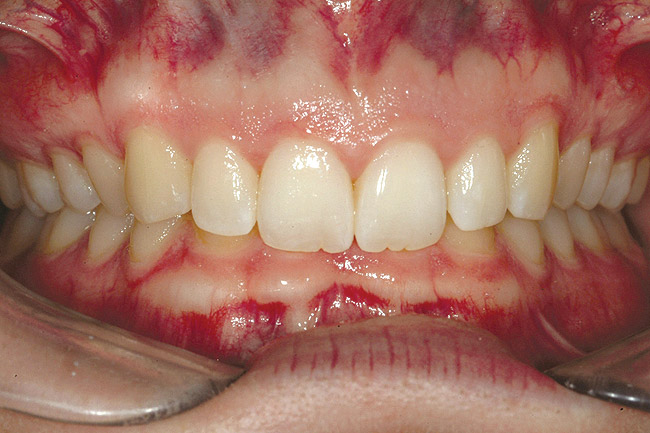

Fig 2 (and Fig 3). Corticotomy SFOT. The patient presented with unesthetic anterior bridgework that was placed at age 14 to compensate for congenitally missing Nos. 7 and 10.

Figure 2

Fig 3 (and Fig 2). Corticotomy SFOT. The patient presented with unesthetic anterior bridgework that was placed at age 14 to compensate for congenitally missing Nos. 7 and 10.

Figure 3